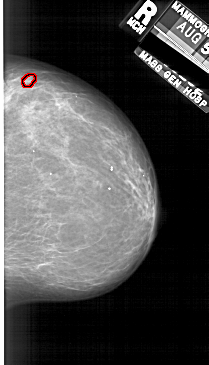

A_1689_1.RIGHT_CC

RIGHT_CC LINES 5836 PIXELS_PER_LINE 3331 BITS_PER_PIXEL 12 RESOLUTION 43.5 OVERLAY

FILE: A_1689_1.RIGHT_CC.OVERLAY

TOTAL_ABNORMALITIES 1

ABNORMALITY 1

LESION_TYPE MASS SHAPE OVAL MARGINS CIRCUMSCRIBED

ASSESSMENT 4

SUBTLETY 3

PATHOLOGY BENIGN

TOTAL_OUTLINES 1

BOUNDARY